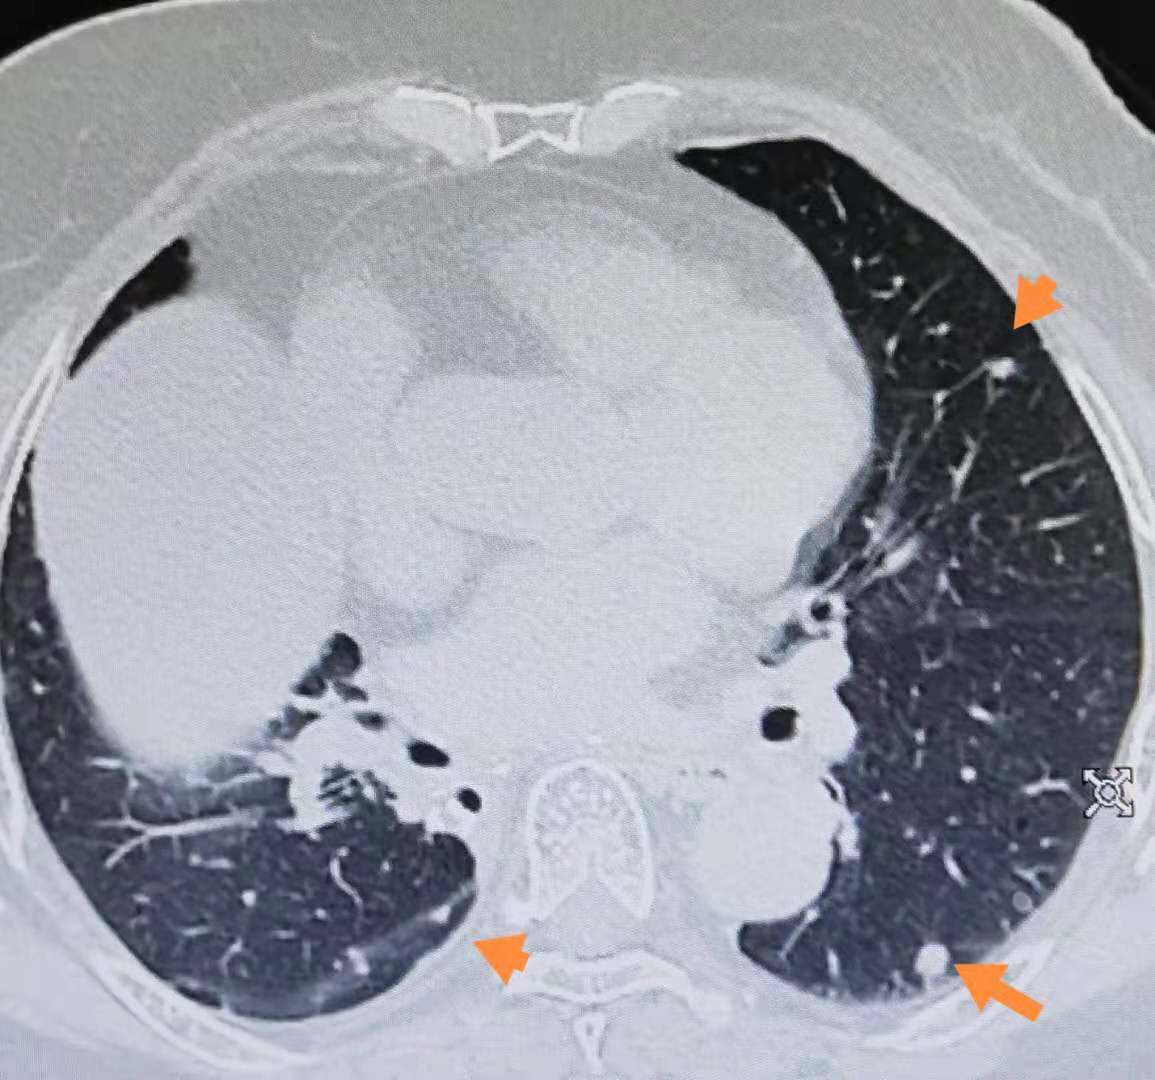

该患者基因检测无敏感基因突变 , PDL1表达低于1% , 术后予以培美曲塞联合卡铂及安维汀化疗六周期 。 2019年07月患者复查CT提示肺内多发结节 , 考虑转移 。 见图4、5、6 。 于是选择二线紫杉类联合铂类化疗 , 2020年12月肺结节增多 , 增大 , 再次进展 , 由于体质较差 , 予以三线安罗替尼口服 , 目前安罗替尼口服过程中 , 预计生存时间低于6个月 。